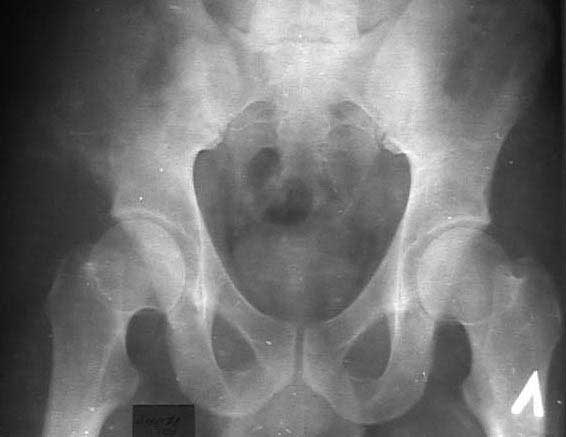

И 2010 год